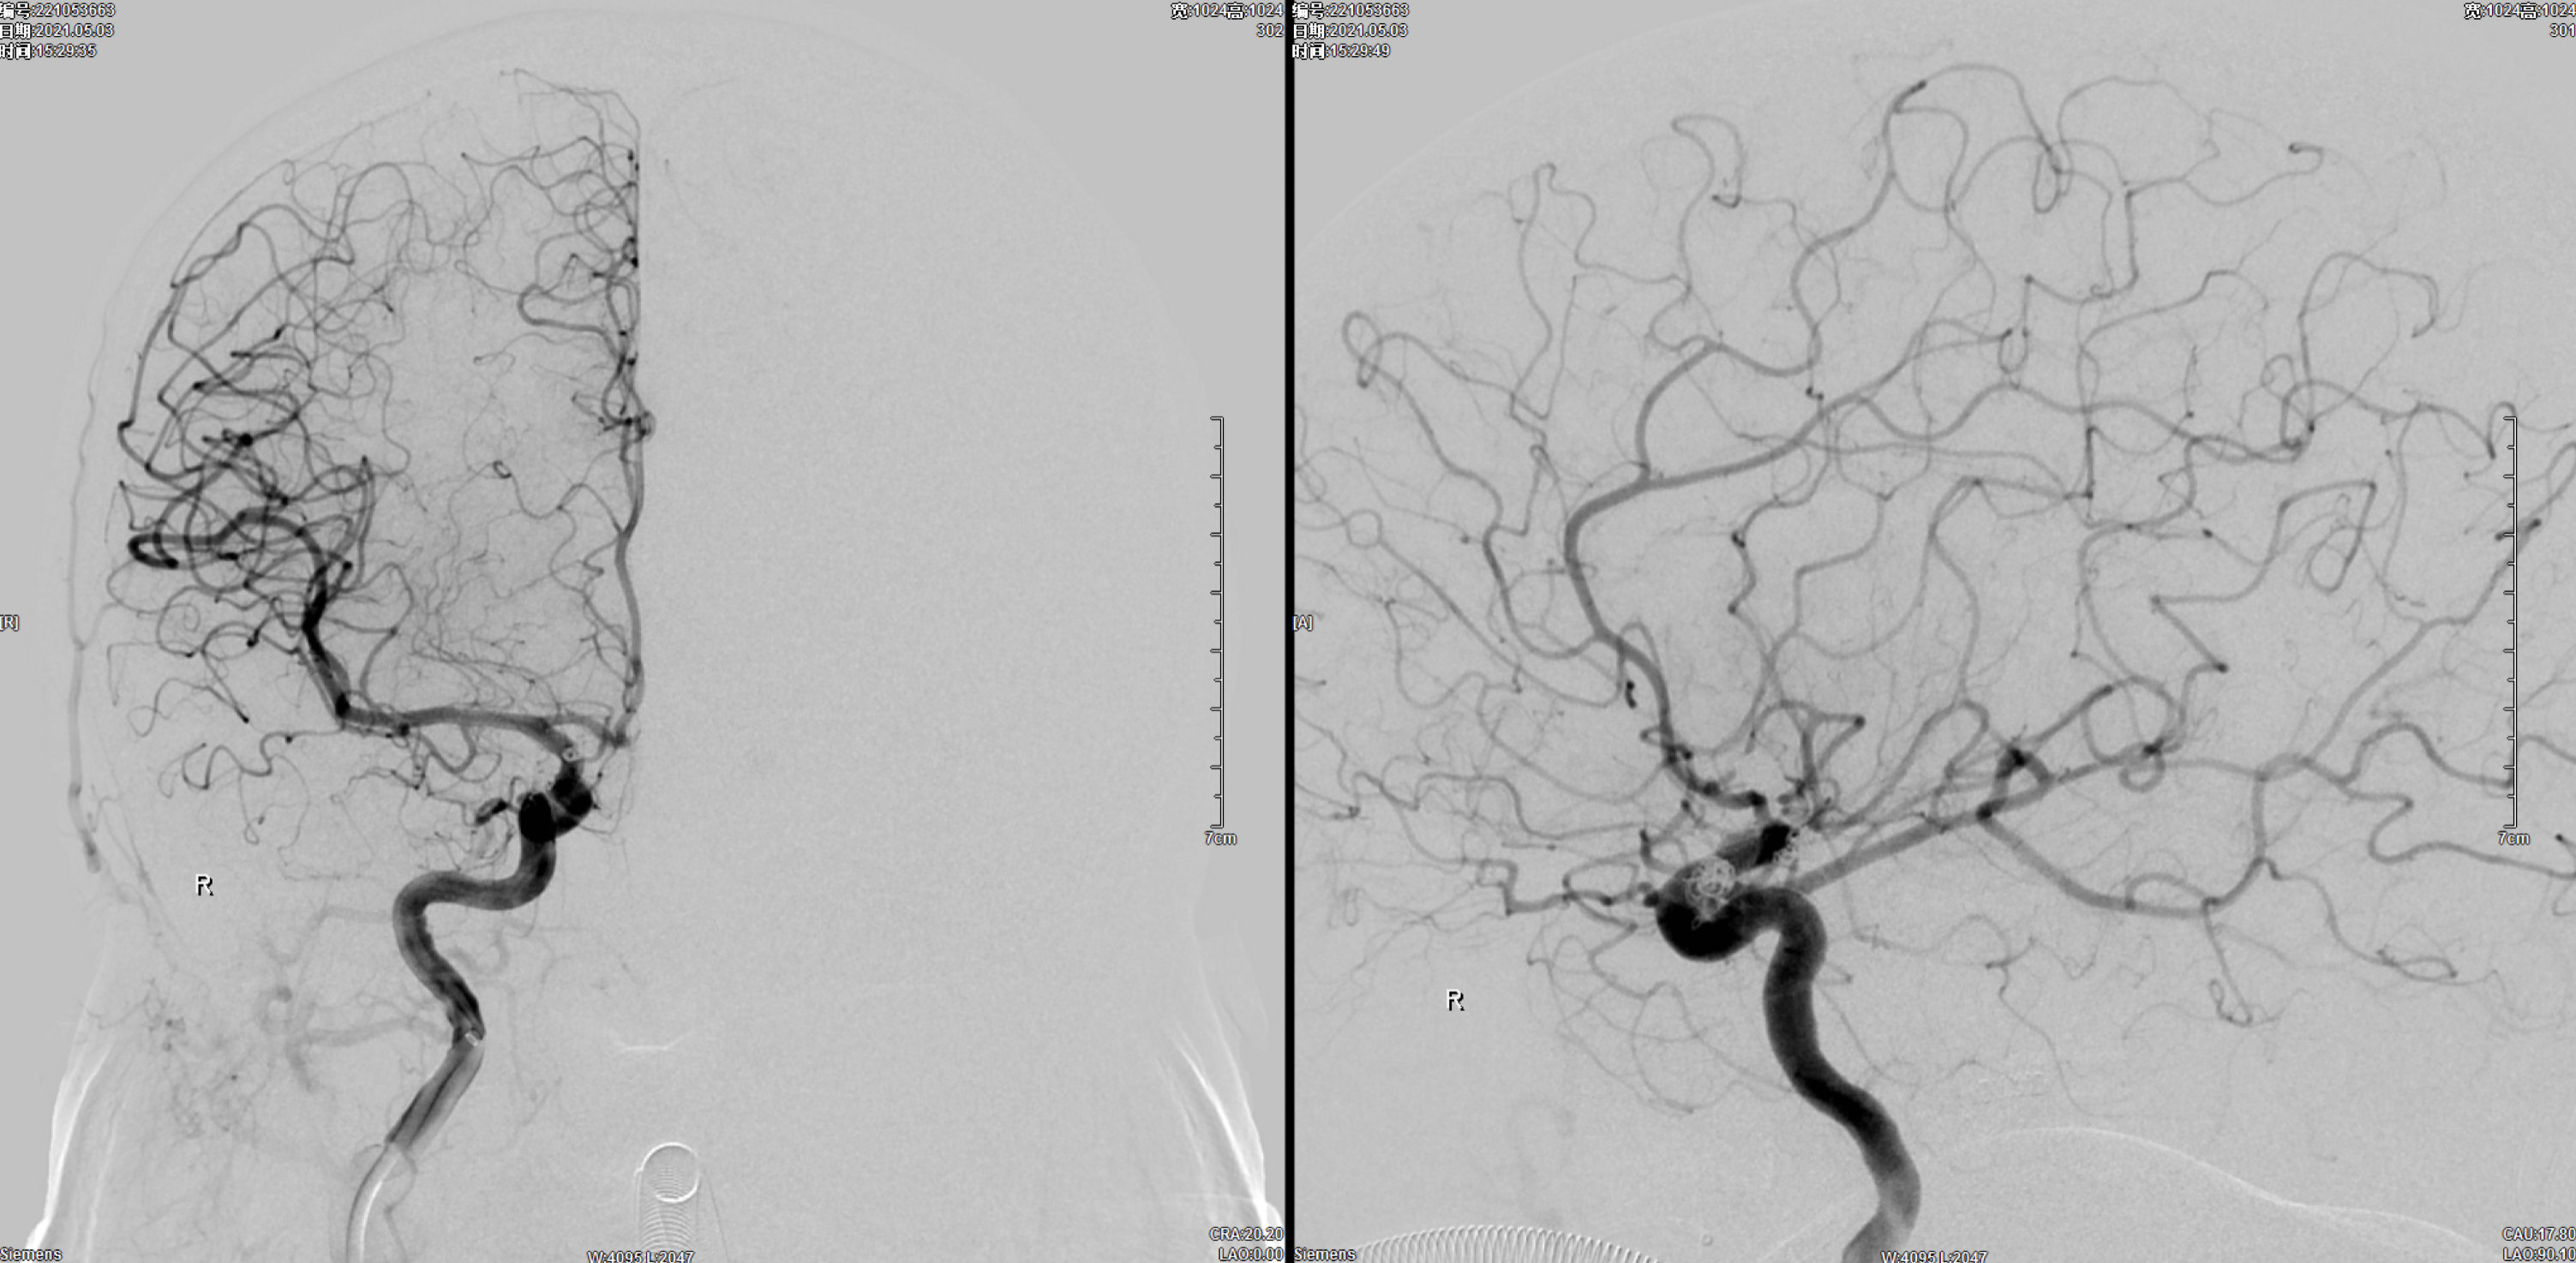

右侧颈内动脉正侧位造影:颈内动脉多发动脉瘤(眼动脉段及后交通段)。

左侧颈内动脉正侧位造影:颈内动脉后交通动脉瘤。

术后右侧颈内动脉正侧位造影:动脉瘤栓塞完全!

术后三维旋转造影:动脉瘤栓塞完全!